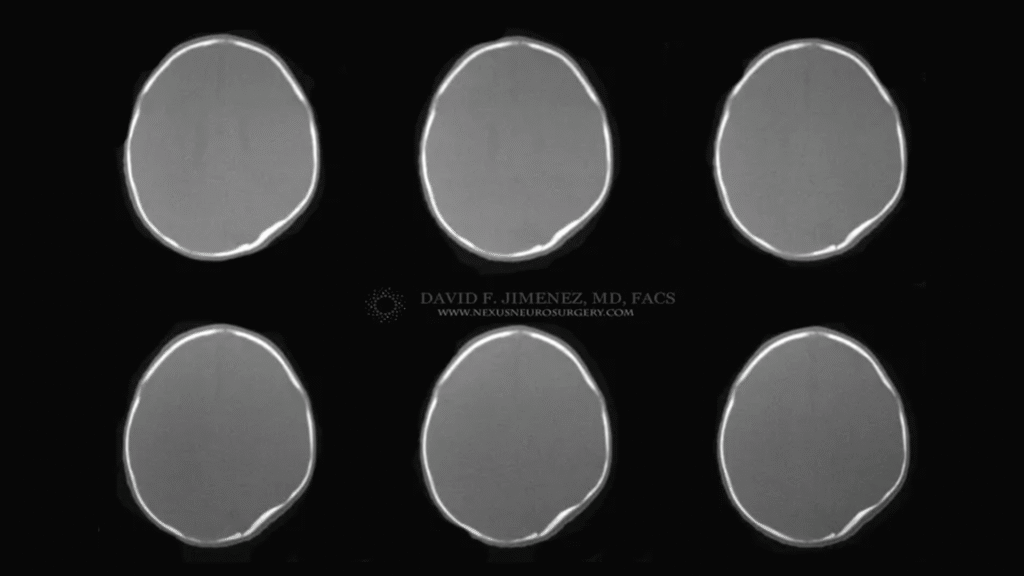

At El Paso Craniofacial Team, the primary treatment for craniosynostosis is surgery. First performed in the late 1800s, surgical approaches have continued to evolve and improve. The two main approaches are Calvarial Vault Remodel (CVR) and endoscopic-assisted surgery, with each tailored to the child’s age, the affected suture, and the severity of the condition.